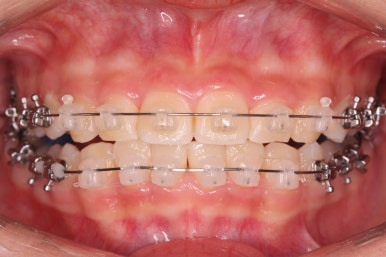

윗니에도 이제 장치를 모두 붙였습니다. 아래쪽은 어느 정도 가지런해지고 나면 부족한 자리를 만들어주기 시작합니다.

부산치아교정잘하는곳 키다리아저씨치과에서 이번 환자분에 사용한 장치는 데이몬 클리어라고 하는 세라믹 자가결찰 장치입니다. 세라믹 자가결찰 장치 중에서 철사를 잡아주는 CAP 부위까지 세라믹으로 되어있어 가장 심미적인 장치라고 볼 수 있습니다.

특히 웃을 때 철사 이외에는 장치가 크게 눈에 띄지 않아서 심미성을 원하시는 분들이 많이 선택을 하는 장치입니다.

부산치아교정잘하는곳 키다리아저씨치과에서는 치아가 올라오자마자 장치를 부착하여 가지런하게 해줍니다. 이제 어느 정도 큰 그림은 그려졌다고 보시면 되겠습니다.

어느 정도 큰 그림이 그려졌으면 중앙선이라든지 치아의 디테일한 면을 더 수정하고 마무리하게 되겠습니다.